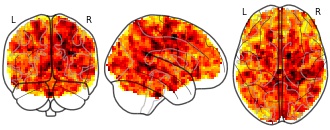

Effects of bariatric surgery on resting state functional connectivity of the...

- neurovault.org

niftiUpdated Mar 22, 2021+ more versions Share

Share Facebook

Facebook Twitter

Twitter EmailClick to copy linkLink copied

EmailClick to copy linkLink copied Cite(2021). Effects of bariatric surgery on resting state functional connectivity of the NAcc (reward network) and PCC (default mode network): Effect of average BMI (negative) on PCC connectivity [Dataset]. http://identifiers.org/neurovault.image:441773niftiAvailable download formatsUnique identifierhttps://identifiers.org/neurovault.image:441773Dataset updatedMar 22, 2021License

Cite(2021). Effects of bariatric surgery on resting state functional connectivity of the NAcc (reward network) and PCC (default mode network): Effect of average BMI (negative) on PCC connectivity [Dataset]. http://identifiers.org/neurovault.image:441773niftiAvailable download formatsUnique identifierhttps://identifiers.org/neurovault.image:441773Dataset updatedMar 22, 2021LicenseCC0 1.0 Universal Public Domain Dedicationhttps://creativecommons.org/publicdomain/zero/1.0/

License information was derived automaticallyDescriptionModel EA3: FC ~ average BMI + change BMI + average logmFD + change logmFD + age + sex

Collection description

Obesity imposes serious health risks and involves alterations in resting-state functional connectivity of brain networks involved in eating behavior. Bariatric surgery is an effective treatment, but its effects on functional connectivity are still under debate. In this pre-registered study, we investigated the effects of bariatric surgery on major resting-state brain networks (reward and default mode network) in a longitudinal controlled design.

33 bariatric surgery patients and 15 obese waiting-list control patients (37 females; aged 44.15 ± 11.86 SD years (range 21-68)) underwent magnetic resonance imaging at baseline, after 6 and 12 months. We conducted a pre-registered whole-brain time-by-group interaction analysis, and a time-by-group interaction analysis on within-network connectivity (https://osf.io/f8tpn/, https://osf.io/59bh7/). In exploratory analyses, we investigated the effects of weight loss and head motion.

Bariatric surgery compared to waiting did not significantly affect functional connectivity (FWE-corrected p > .05), neither whole-brain nor within-network. In exploratory analyses, surgery-related BMI decrease (FWE-corrected p = .041) and higher average head motion (FWE-corrected p = .021) resulted in significantly stronger connectivity of the reward network with medial posterior frontal regions.

This pre-registered well-controlled study did not support a strong effect of bariatric surgery, compared to waiting, on major resting-state brain networks after 6 months. Exploratory analyses indicated that head motion might have confounded the effects. Data pooling and more rigorous control of within-scanner head motion during data acquisition are needed to substantiate effects of bariatric surgery on brain organization.Subject species

homo sapiens

Modality

fMRI-BOLD

Analysis level

group

Cognitive paradigm (task)

rest eyes closed

Map type

Z